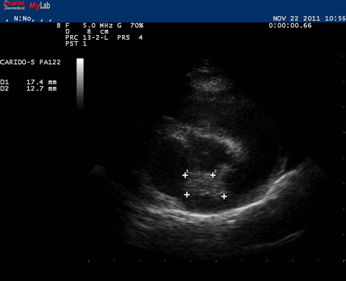

第一次化疗:患犬体重10.2kg,静注多柔比星10mg,并辅助泼尼松等其他药物。化疗后第3天晚上患犬出现两次心悸症状,饮水后情况有所好转。此症状一般发生在晚上,在化疗后的第4-5天最严重,以后慢慢好转,第7天后再没有出现此症状。期间患犬精神状态,体温,饮食和排便都正常。因为给与泼尼松,患犬饮水量和排尿量有所增加。对患犬进行心脏彩超检查发现左心房壁有赘生物(见图5)

图 5  左心房壁赘生物彩超图。白色“+”所标志区域表示赘生物。

阿霉素具有广谱抗肿瘤作用,常见适应症是淋巴瘤,骨肉瘤,血管肉瘤和多种癌症。其副反应除了一般的骨髓抑制和胃肠道反应外,还有急性反应包括过敏反应,外渗损伤和少见的心率失常(中老年犬)。该病例中患犬主要表现的副反应是心律失常,即在第一次阿霉素治疗后的第3-5天表现明显的心悸症状,可能与其心脏左心房有赘生物有关。对患犬进行心电图检查没有明显的异常。第二次使用阿霉素后再没有出现症状。实验表明如果药物被缓慢注射超过20min,心律不齐和过敏症会减轻。对于心脏功能不好的动物在使用阿霉素前应进行充分的心脏检查,若有异常,应该由心脏病专家评估后进行化疗。可以在化疗前给与一些心脏保护类药物。